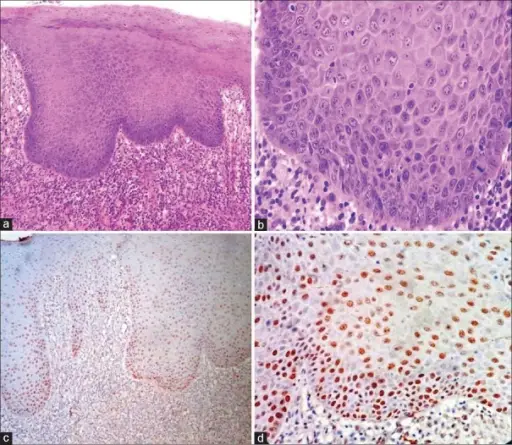

Hairy Leukoplakia

Hairy leukoplakia (HL) is a histological manifestation of HIV infection and is distinguished by parakeratosis of the oral mucosa, hyperkeratosis, keratinization of the epithelium, and numerous intracellular inclusion bodies made up of lipid vacuoles, concentric lamellar structures, and occasionally viral particles within macrophages.

Oral sores are very contagious and frequently lead to the development of systemic diseases.